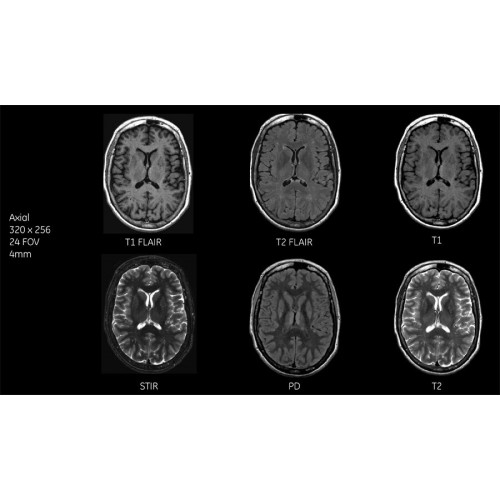

Детализация изображений

Система SIGNA Pioneer воплощает поразительные достижения в области визуализации. Передовая технология Total Digital Imaging (TDI) позволяет добиться большей четкости изображений и на четверть повысить соотношение сигнал/шум.

TDI построена на трех базовых компонентах:

• Технология Direct Digital Interface (DDI) использует независимый аналого-цифровой преобразователь для оцифровки сигнала от каждого из 97 радиочастотных каналов, что обеспечивает значительное увеличение качества за счет уменьшения фонового шума.

• Технология Digital Micro Switching (DMS) — это следующее поколение технологий радиочастотных катушек, основанное на замене аналоговых схем блокировки сверхбыстрыми микропереключателями (MEMS), что делает возможным быстрое переключение катушек для дальнейшего расширения возможностей визуализации с нулевым TE.

• Технология Digital Surround Technology (DST) — это новая технология объемной оцифровки данных, объединяющая сигналы от каждого элемента катушки. Прекрасное соотношение сигнал/шум и чувствительность поверхностных катушек в сочетании с превосходной однородностью и высокой проникающей способностью встроенной радиочастотной катушки — все это позволяет создавать качественные изображения не только позвоночника, но и всего тела.

Помимо технологии 97 РЧ-каналов, SIGNA Pioneer использует магнит 3.0Т высокой однородности, предназначенный для повышения качества визуализации во всех областях, а также закладывающий прочный фундамент для долгосрочных инвестиций и роста клинических возможностей.

Благодаря революционному программному пакету Silent Suite уровень шума снижается до 77 дБ, что всего на 3 дБ выше уровня окружающей среды. Программный пакет Silent Suite теперь включает полный пакет приложений для исследования ЦНС (T1, T2 FLAIR, DWI10, МРА). Кроме того, мы расширили возможности визуализации Silent за пределы ЦНС для исследований скелетно-мышечной системы и позвоночника. Silent Suite – платформа, содержащая в себе все импульсные последовательности для бесшумного сканирования.